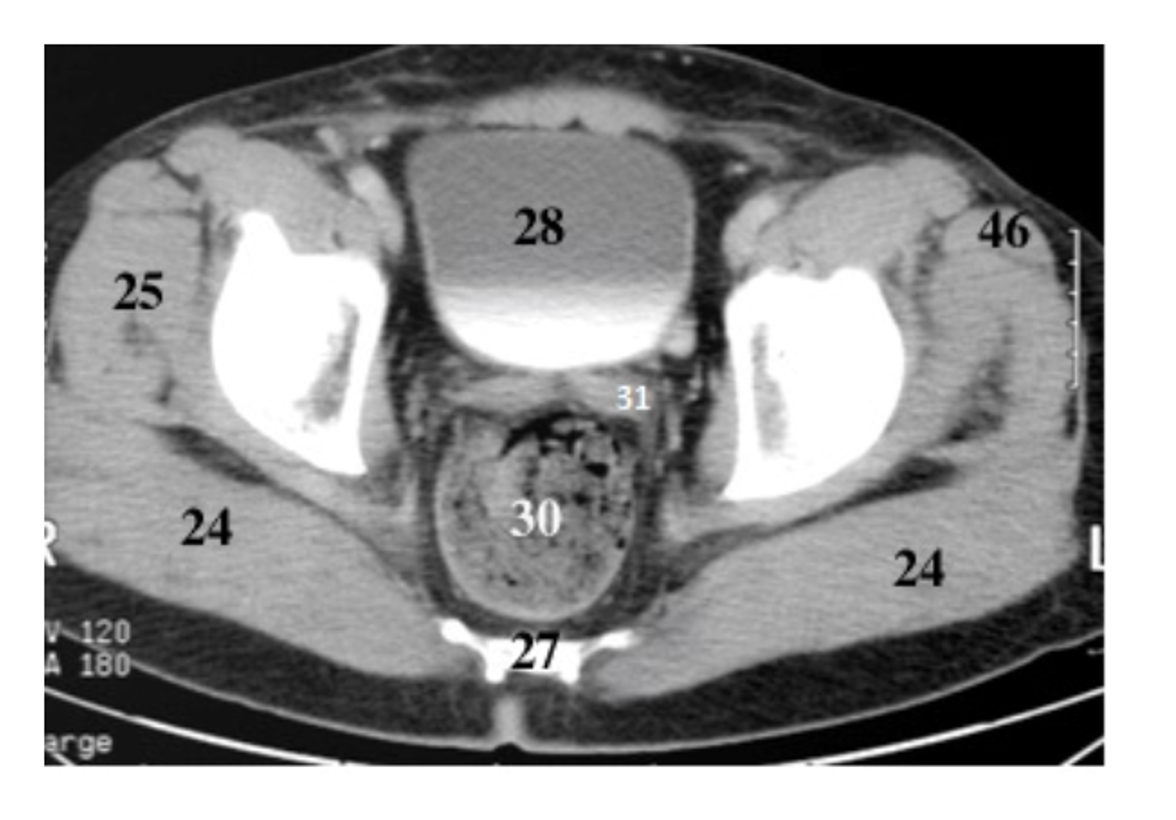

29

pubis

30

ishium

rectum

28

bladder

31

seminal vesicles

28 women

cervix

25 women

uterus